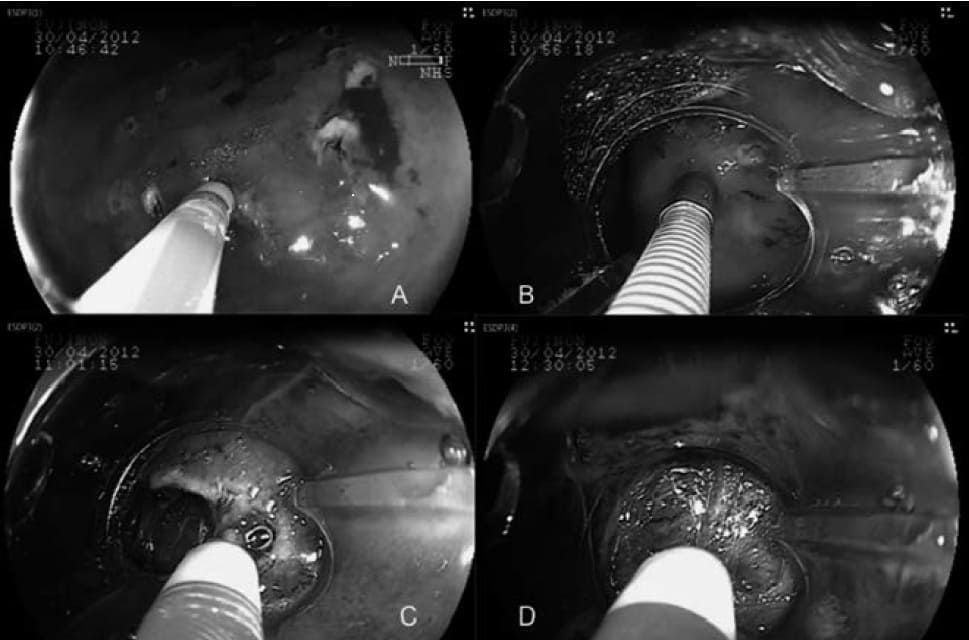

Bisturí de disección endoscópica submucosa (DSE)